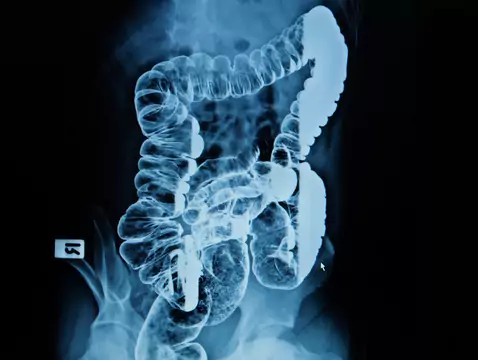

Le cancer colorectal est généralement un adénocarcinome. Il est plus fréquent chez les hommes que chez les femmes. Il est rarement découvert avant l'âge de 40 ans, mais ces dernières années ont...